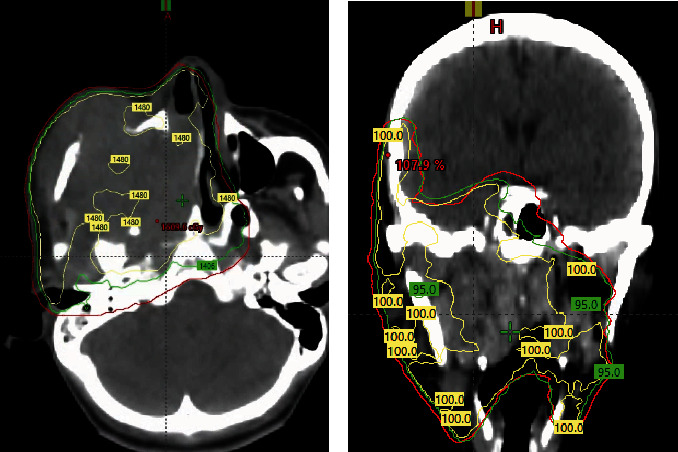

Sinonasal malignancies (SNMs) are rare heterogeneous malignancies that frequently present with locally advanced disease. The prognosis is poor when the disease is considered extensive and unresectable. In such cases, a high-dose palliative radiotherapy regimen is often required, but the ideal dose and fractionation have not been established. We detail a 33-year-old male who initially presented with a progressively growing mass over the right cheek. A biopsy of the lesion revealed squamous cell carcinoma (SCC). Imaging revealed a very advanced and unresectable disease with the involvement of several head and neck subsites. He progressed further after receiving induction chemotherapy from an outside institution. The patient requested prompt tumor and symptom control to travel back to his home country. We offered him high-dose split-course palliative radiotherapy in the form of a quad Shot of 14.80 Gy in four fractions twice daily, followed by 30 Gy in five fractions every other day with a 2-week interval. Treatment resulted in excellent clinical response with symptomatic relief in a short time, and the patient could travel back home safely.